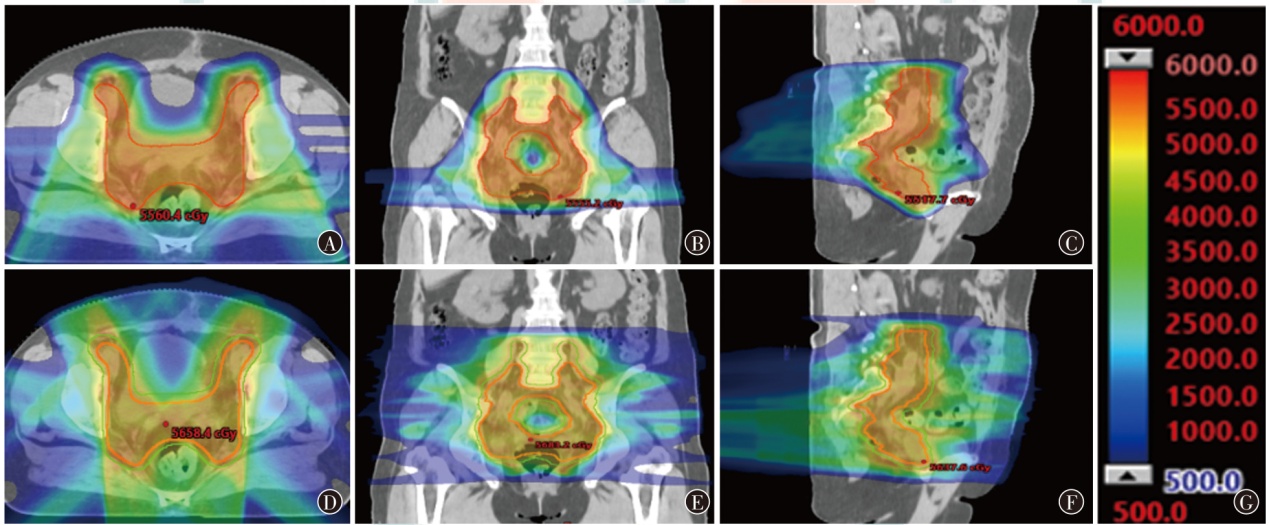

目的探讨质子调强放疗(IMPT)和光子固定野调强放疗(IMRT)应用于典型腹盆部肿瘤的剂量学特点。方法以2024年1月至6月山东省肿瘤防治研究院(山东省肿瘤医院)收治的3例腹盆部肿瘤(肝癌、宫颈癌和前列腺癌各1例)患者为研究对象,根据临床靶区和危及器官限值的要求,分别设计IMPT和IMRT两种放疗计划。评估3例患者两种放疗计划的靶区适形指数(CI)、均匀性指数(HI)和梯度指数(GI)及危及器官剂量学参数,通过评估体内10%、30%和50%处方剂量区域的体积比较患者体内额外的剂量沉积。结果3例患者IMPT计划的CI值(分别为0.61、0.62和0.43)、HI值(分别为0.053、0.075和0.020)、GI值(分别为3.45、2.63和3.80)均小于IMRT计划(CI分别为0.82、0.81和0.86;HI分别为0.060、0.120和0.080;GI分别为7.28、4.76和4.66)。与IMRT计划相比,在肝癌患者中,IMPT计划可使正常肝组织和右肾的Dmean及脊髓的Dmax分别降低37.8%、78.5%和13.2%;在宫颈癌患者中,IMPT计划可使小肠的V30,膀胱、直肠、骨髓的Dmean和脊髓的Dmax分别降低22.0%、15.7%、14.3%、12.6%和4.8%;在前列腺癌患者中,IMPT计划可使膀胱和直肠的Dmean分别降低14.9%和36.5%,但IMPT计划使左侧股骨头的Dmean及V40分别升高了35.3%和6.1%,使右侧股骨头的Dmean及V40分别升高了23.6%和10.8%。3例患者体内10%、30%和50%的处方剂量区域所占的体积,IMPT计划比IMRT计划减少了48.9%~64.8%、22.0%~47.0%、22.0%~57.7%。结论腹盆部肿瘤的IMPT和IMRT计划比较,IMPT计划在降低正常肝脏、肾脏、脊髓、小肠、直肠和膀胱等器官的剂量方面有优势;对于股骨头的剂量,IMPT计划优势并不明显;IMPT计划可显著减少患者体内额外的剂量沉积。

ObjectiveTo explore the dosimetric characteristics of intensity modulated proton therapy (IMPT) and intensity modulated radiation therapy (IMRT) for typical abdominal and pelvic tumors.MethodsThree patients with abdominal and pelvic tumors (one case each of liver cancer,cervical cancer,and prostate cancer) admitted to Shandong Cancer Hospital and Institute from January to June 2024 were selected as the research subjects. IMPT and IMRT plans were designed for each case based on clinical target volume (CTV) and organs at risk (OARs) constraints. Dosimetric parameters,including conformity index (CI),homogeneity index (HI),and gradient index (GI) for target coverage,as well as OARs dose metrics,were evaluated. The volume of additional dose deposition in the body was compared by assessing regions receiving 10%,30%,and 50% of the prescription dose.ResultsFor all three cases,IMRT plan demonstrated higher CI values (0.82,0.81,and 0.86) compared to IMPT plan (0.61,0.62,and 0.43). IMPT plan yielded lower HI values (0.053,0.075,and 0.020) than IMRT plan (0.060,0.120,and 0.080) and lower GI values (3.45,2.63,and 3.80vs. 7.28,4.76,and 4.66 for IMRT plan). In liver cancer,IMPT plan reduced the Dmeanof normal liver tissues and right kidney by 37.8% and 78.5%,respectively,and decreased the Dmaxof spinal cord by 13.2%. For cervical cancer,IMPT plan reduced the V30of the small bowel by 22.0%,Dmeanof the bladder,rectum and bone marrow by 15.7%,14.3% and 12.6%,and spinal cord Dmaxby 4.8%. In prostate cancer,IMPT plan lowered bladder and rectal Dmeanby 14.9% and 36.5%,respectively,but resulted in an increase of 35.3% and 6.1% in the Dmeanand V40of the left femoral head,respectively,and an increase of 23.6% and 10.8% in the Dmeanand V40of the right femoral head,respectively. IMPT plan reduced the volumes receiving 10%,30%,and 50% of the prescription dose by 48.9%-64.8%,22.0%-47.0%,and 22.0%-57.7%,respectively,compared to IMRT plan.ConclusionsComparison between IMPT and IMRT plans for abdominopelvic tumors: IMPT plan offers advantages in reducing doses to normal organs such as the liver,kidneys,spinal cord,small intestine,rectum,and bladder. However,its advantage is less pronounced regarding the dose to the femoral heads. IMPT plan notably minimizes additional dose deposition within the body.